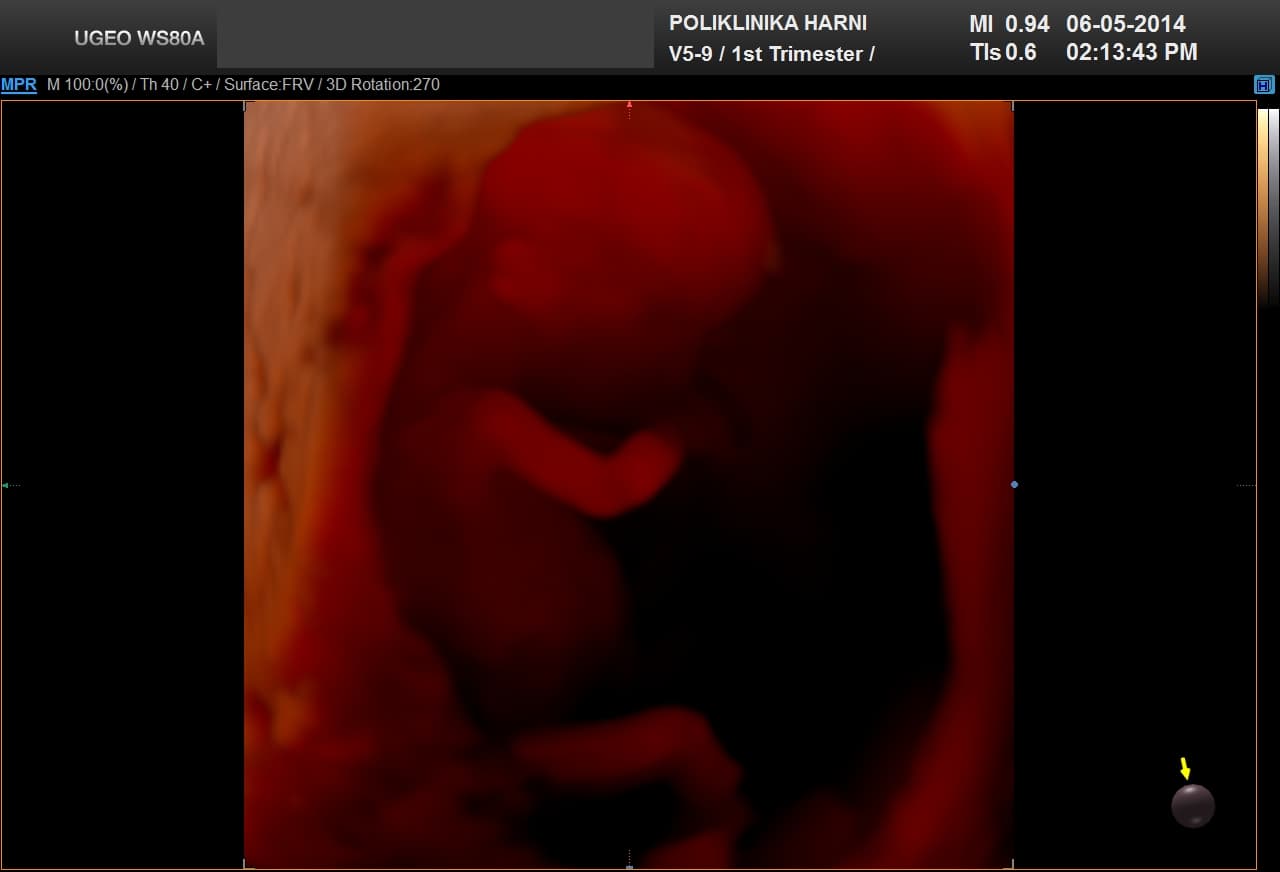

Nakon 2D i 3D ultrazvučnog prikaza, ultrazvučna tehnologija dobila je mogućnost promatranja slika u pokretu tijekom vremena pa je vrijeme označeno četvrtom dimenzijom.

Otuda 4D ultrazvuk označuje trodimenzionalni ultrazvučni prikaz fetalnih pokreta u realnom vremenu.